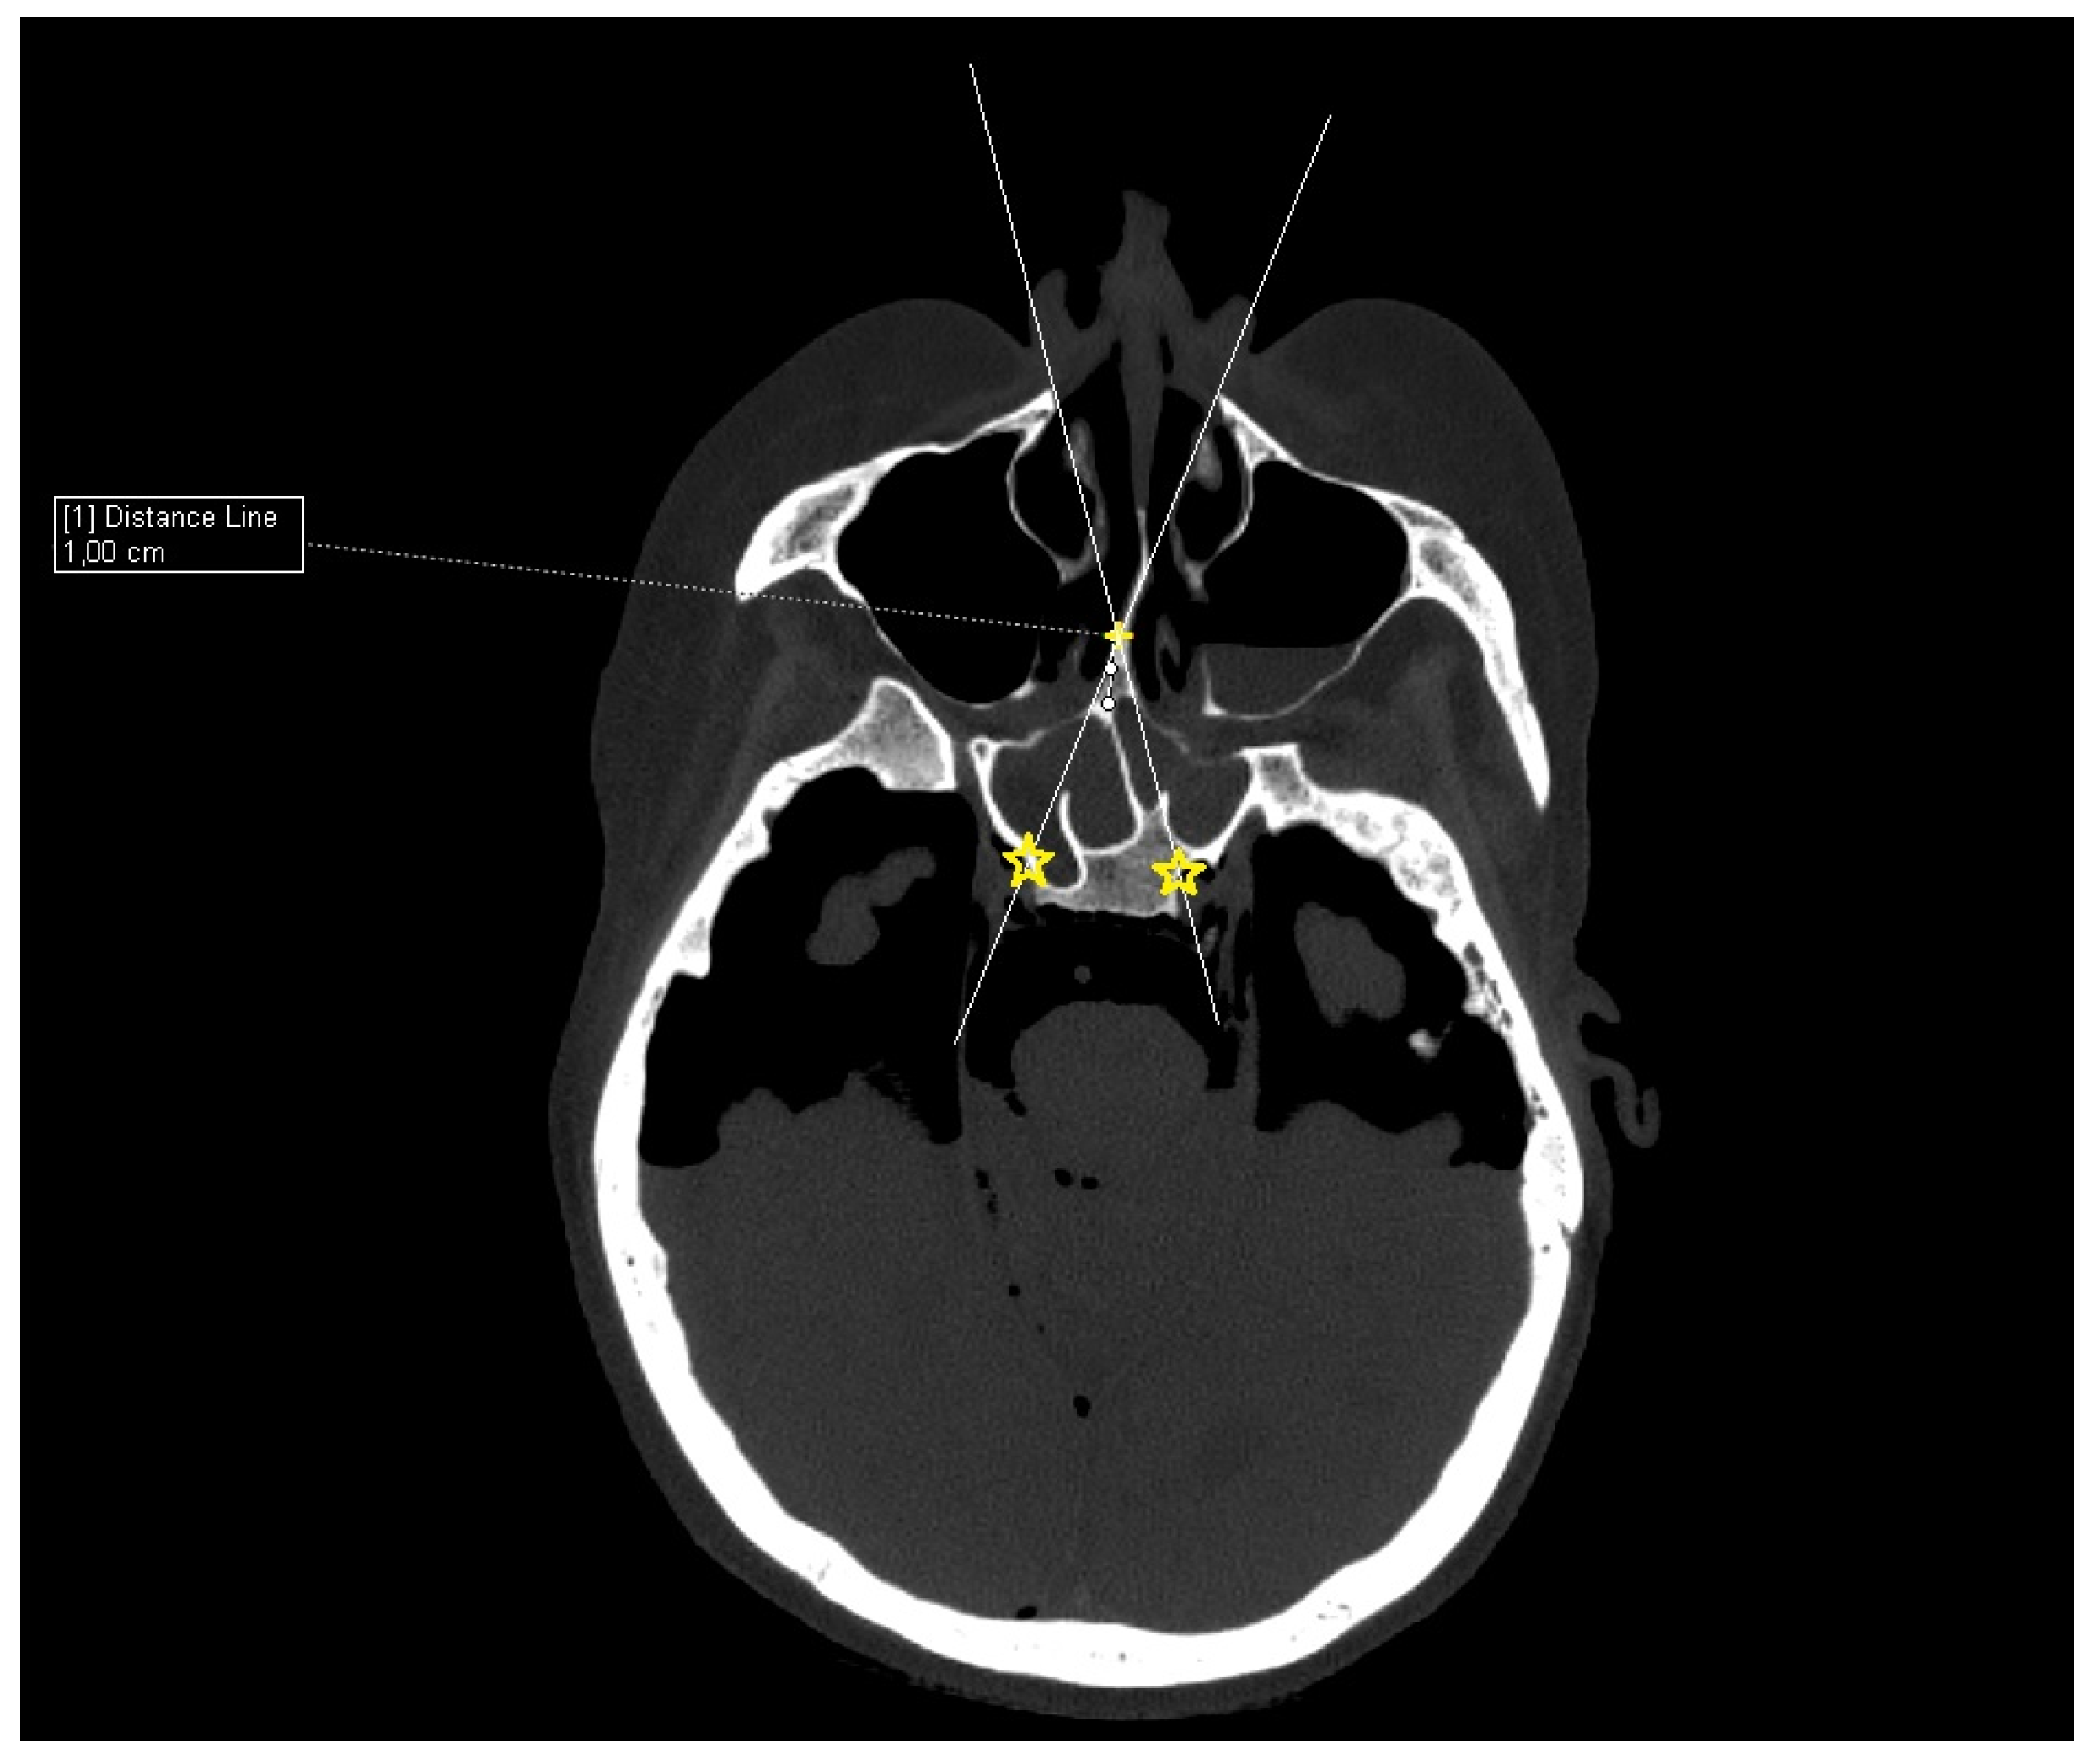

Cadaver CT scan: Two cadaver heads were used for the CT scan measurement. The CT scans were performed on a Siemens Somatom force scanner (Siemens healthineers, Praha, Czech Republic). With each cadaver head, a different size of septal resection was simulated in SyngoVia software (VB40, Siemens healthineers, Praha, Czech Republic). For the simulation, we used HrCT images with a slice thickness of 0.6 mm in a semi-axial view. A virtual 1 cm posterior part septal resection was performed by marking a yellow cross on the nasal septum 1 cm from the anterior sphenoid wall. A white line was drawn to simulate the insertion of a straight instrument. The defined points for this line were the bony lateral part of the nasal aperture and the marked yellow cross on the nasal septum. The place where this ongoing white line crossed the posterior bony edge of the sphenoidal sinus represented the most lateral point that could be reached in the sphenoid sinus with a straight instrument without infracturing the nasal septum. This point was then marked with a yellow star. The same procedure was performed for both nostrils. The same principle and procedure were used for a 2 cm resection simulation with the second cadaver head (Figure 3).

Figure 3. CT scan, semi-axial view, 1 cm distance from anterior sphenoid wall on nasal septum (yellow cross), virtual straight instruments inserted into sphenoid sinus simulating binostril approach (white lines), most lateral area in sphenoid cavity that can be reached with straight instrument with 1 cm septal resection without infracturing the nasal septum (yellow stars).